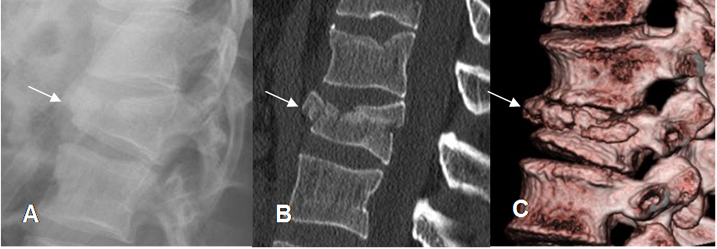

Fig 184. Fractura con TAC

A: Rx lateral, B: TAC reconstrucción sagital y C: TAC reconstrucción en 3D. Fractura por aplastamiento con compromiso de la columna anterior y media y pequeño fragmento retropulsado.